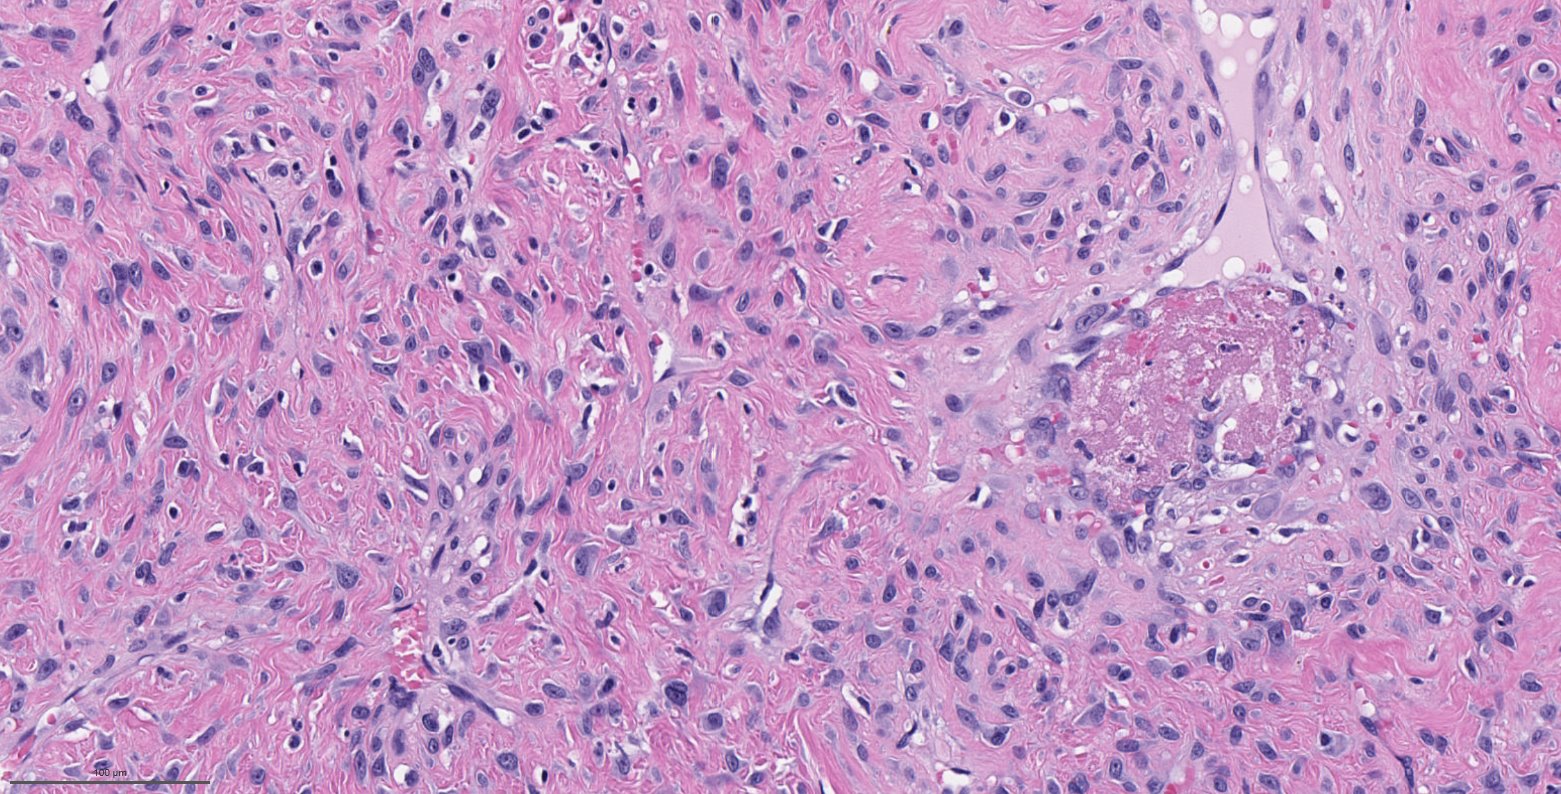

Microscopic (histologic) description

- Benign fibrovascular lesion composed of 2 components

- Vascular space of various sizes, ranging from dilated branching vessel of various thickness to slit-like capillaries

- Fibrous or collagenous stroma with fibroblasts

- Central area of the tumor is typically cellular, composed of fibroblasts or myofibroblasts with spindle, round or stellate morphology

- Stroma can be fibrous, edematous or collagenized

- Fibrinous thrombi may be seen in dilated vessels

- Frequently contain (abundant) mast cells

- Mitotic figures are usually absent

Microscopic (histologic) images

Contributed by Bin Xu, M.D., Ph.D.

Contributed by Kelly Magliocca, D.D.S., M.P.H.